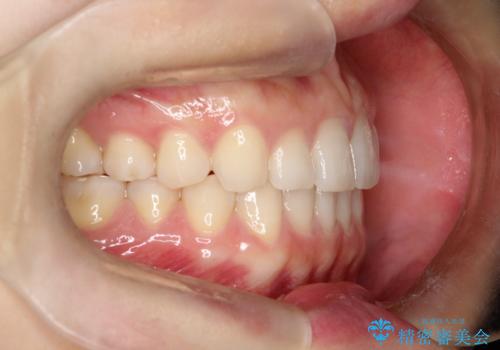

- 前歯のガタガタを綺麗にしたいとのことでインビザラインにて治療を行いました。

治療前は臼歯部反対咬合のため下顎が偏移し正中がずれていましたが、臼歯部反対咬合を改善したことで、正中のズレを改善することができました。